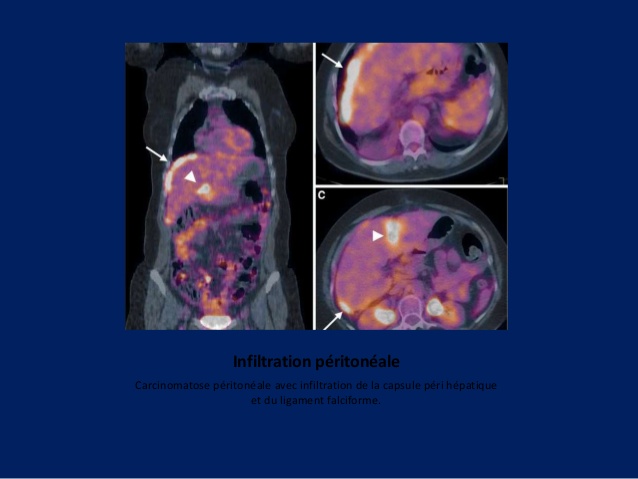

Fiche mémo carcinose péritonéale pour rebondir sur l’atelier acomen des JFMN 2017 carcinose péritonéale